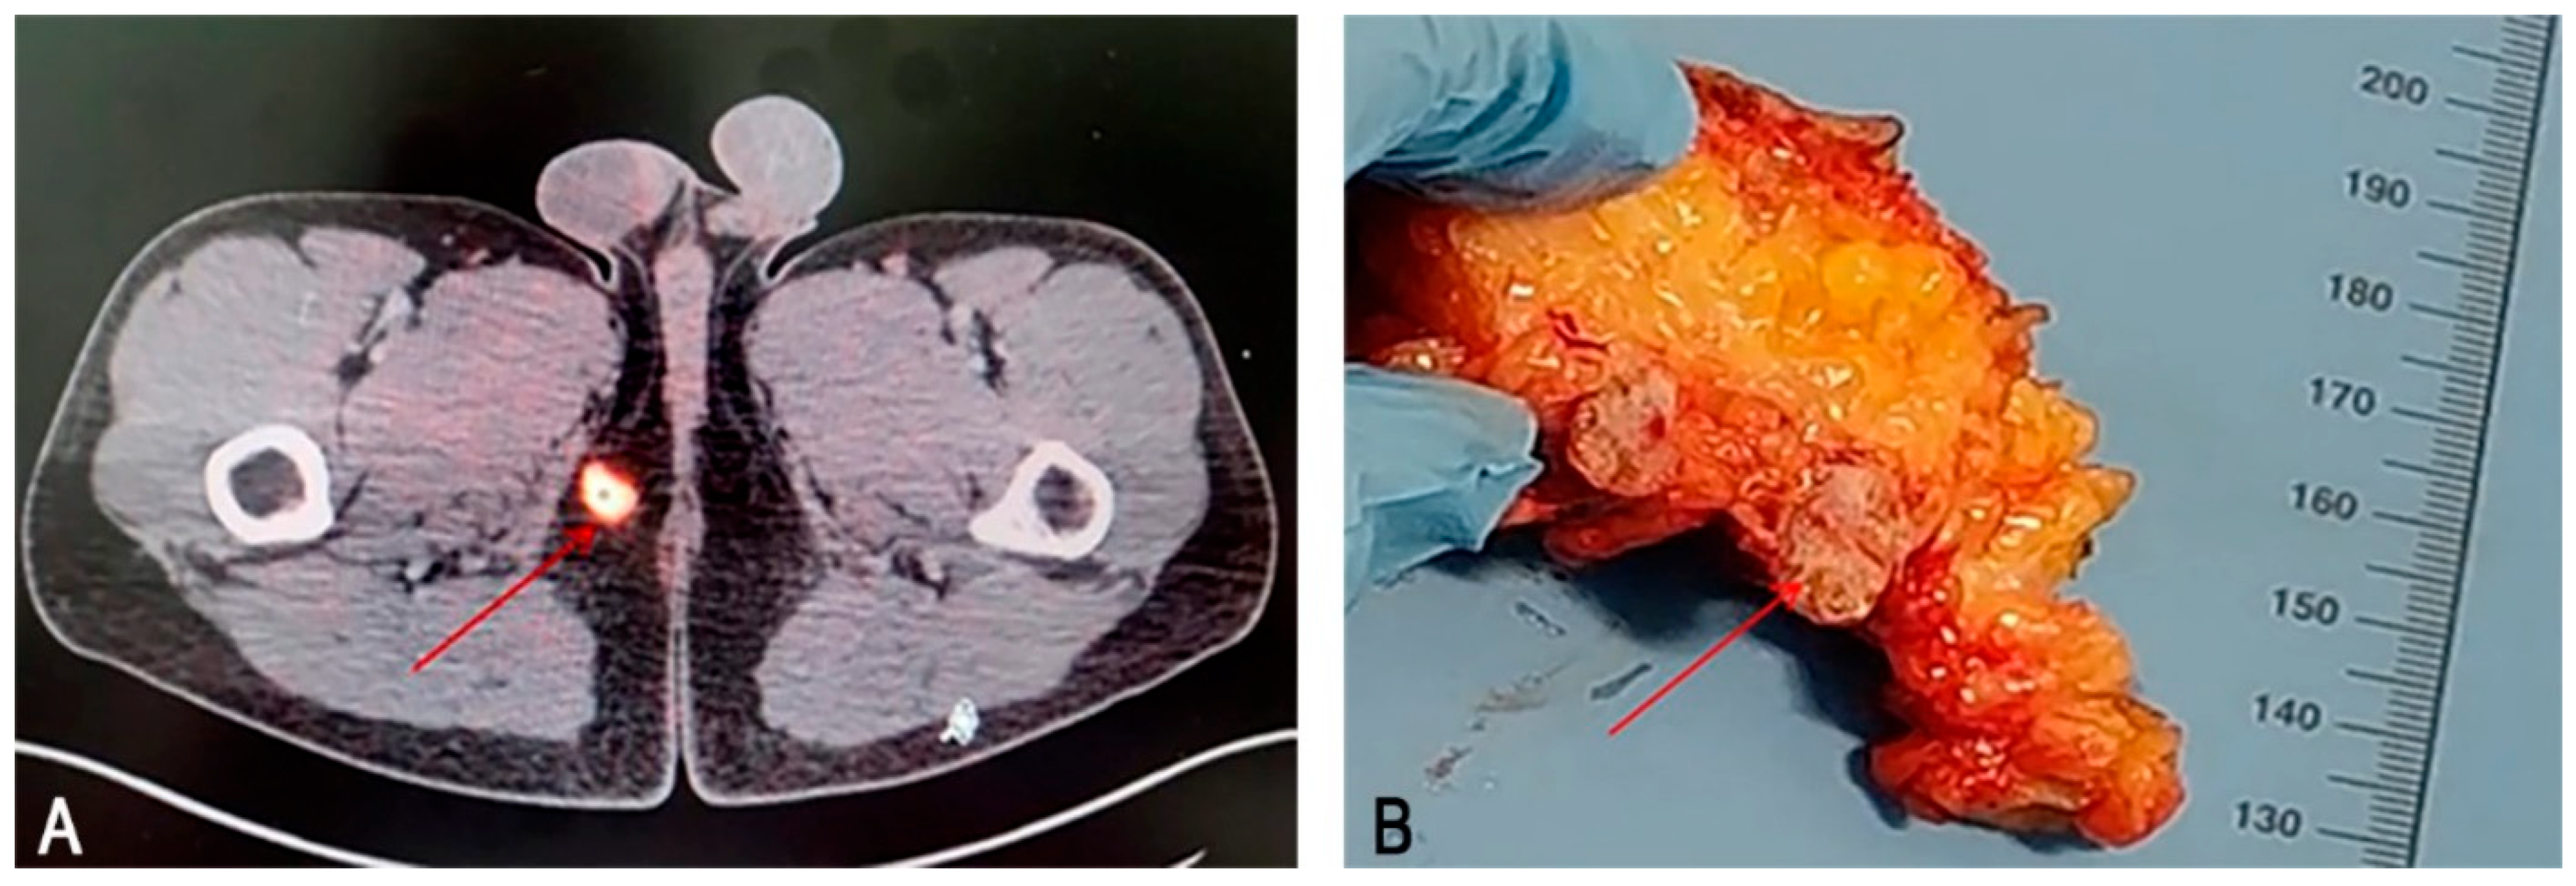

2.1. Case Report